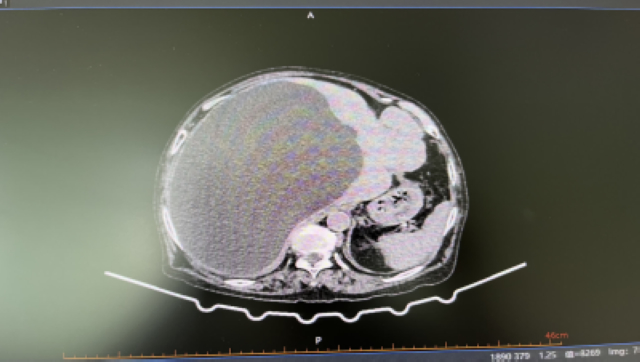

【关注】她体内的“解毒工厂”,却装了一大盆水,原因竟是……

今年91岁的魏婆婆,10年前体检时发现了肝囊肿,当时肝囊肿不大,也没有症状,所以没有进行特殊处理。近1年来,魏婆婆反复出现腹部胀痛不适,上腹部还可以摸到有个包块,并且在渐渐增大。女儿放心不下,便带着魏婆婆来到西南医科大学附属中医医院就诊。入...